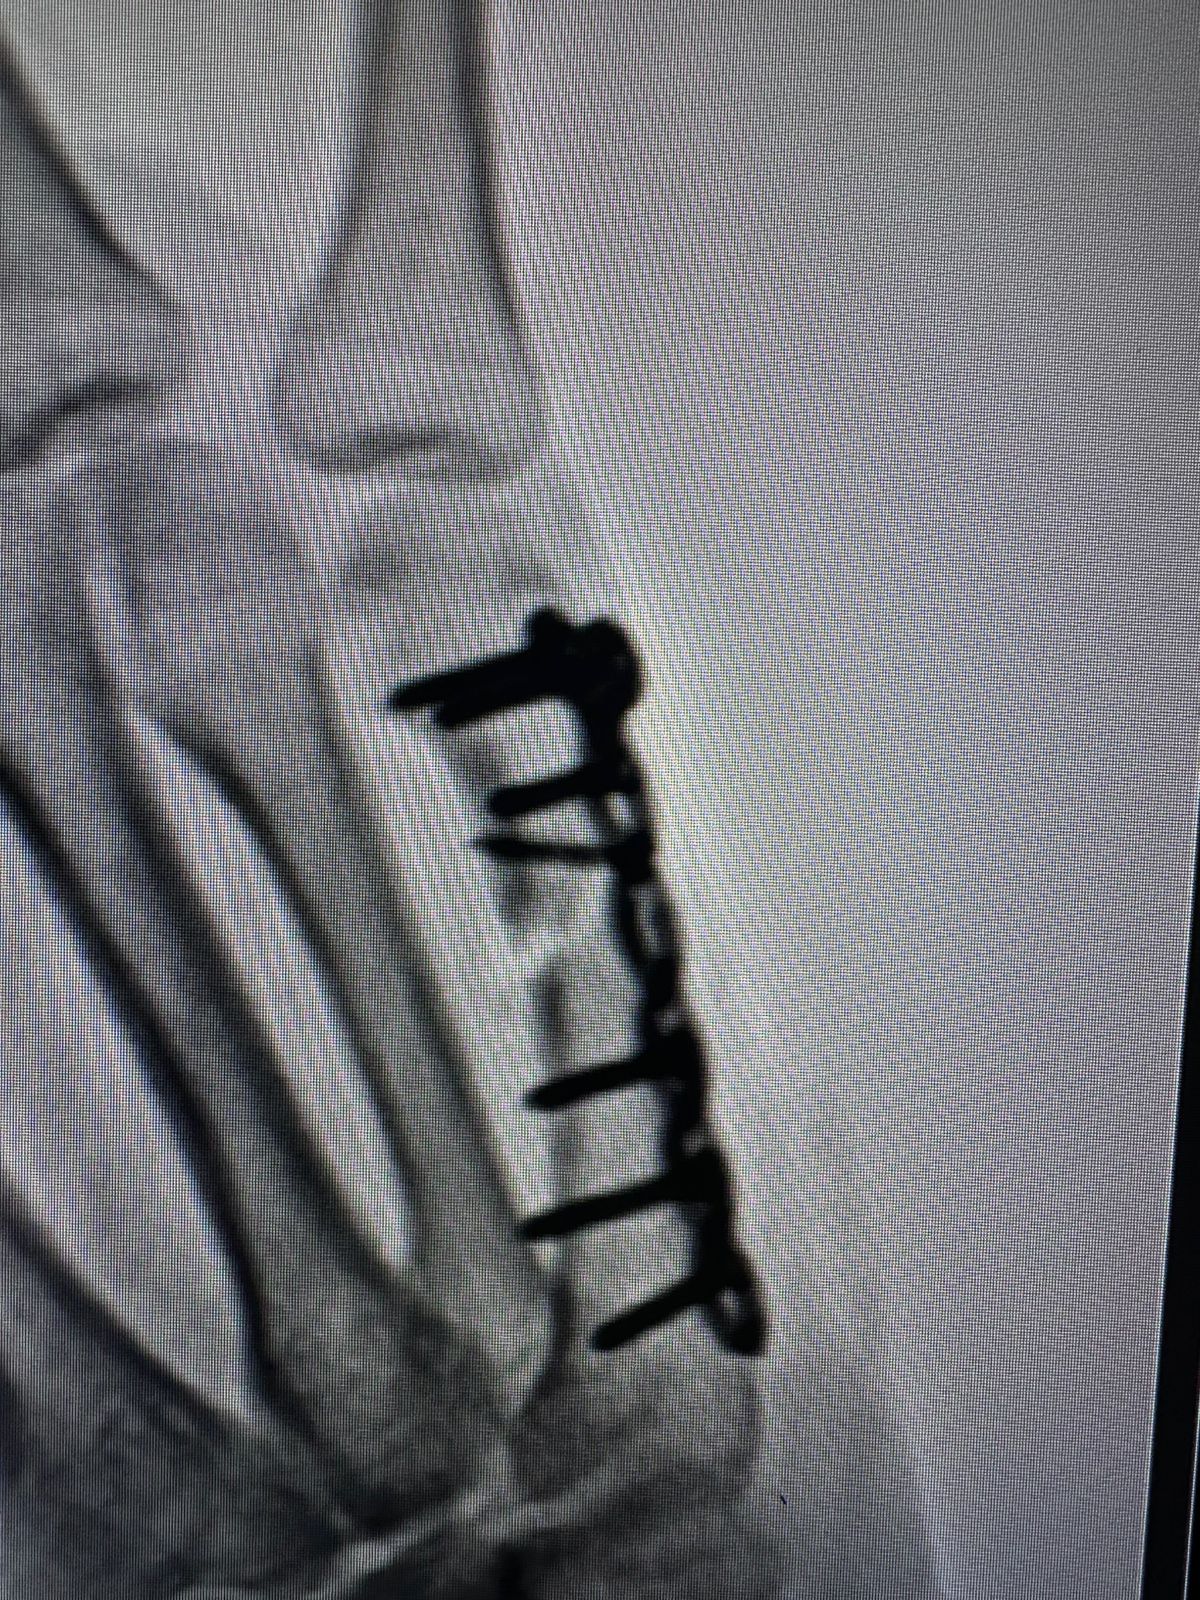

Moments That Mark Meaningful Recovery

Witness real patient transformations at The Ortho Clinic through images that reflect successful treatments and restored mobility.